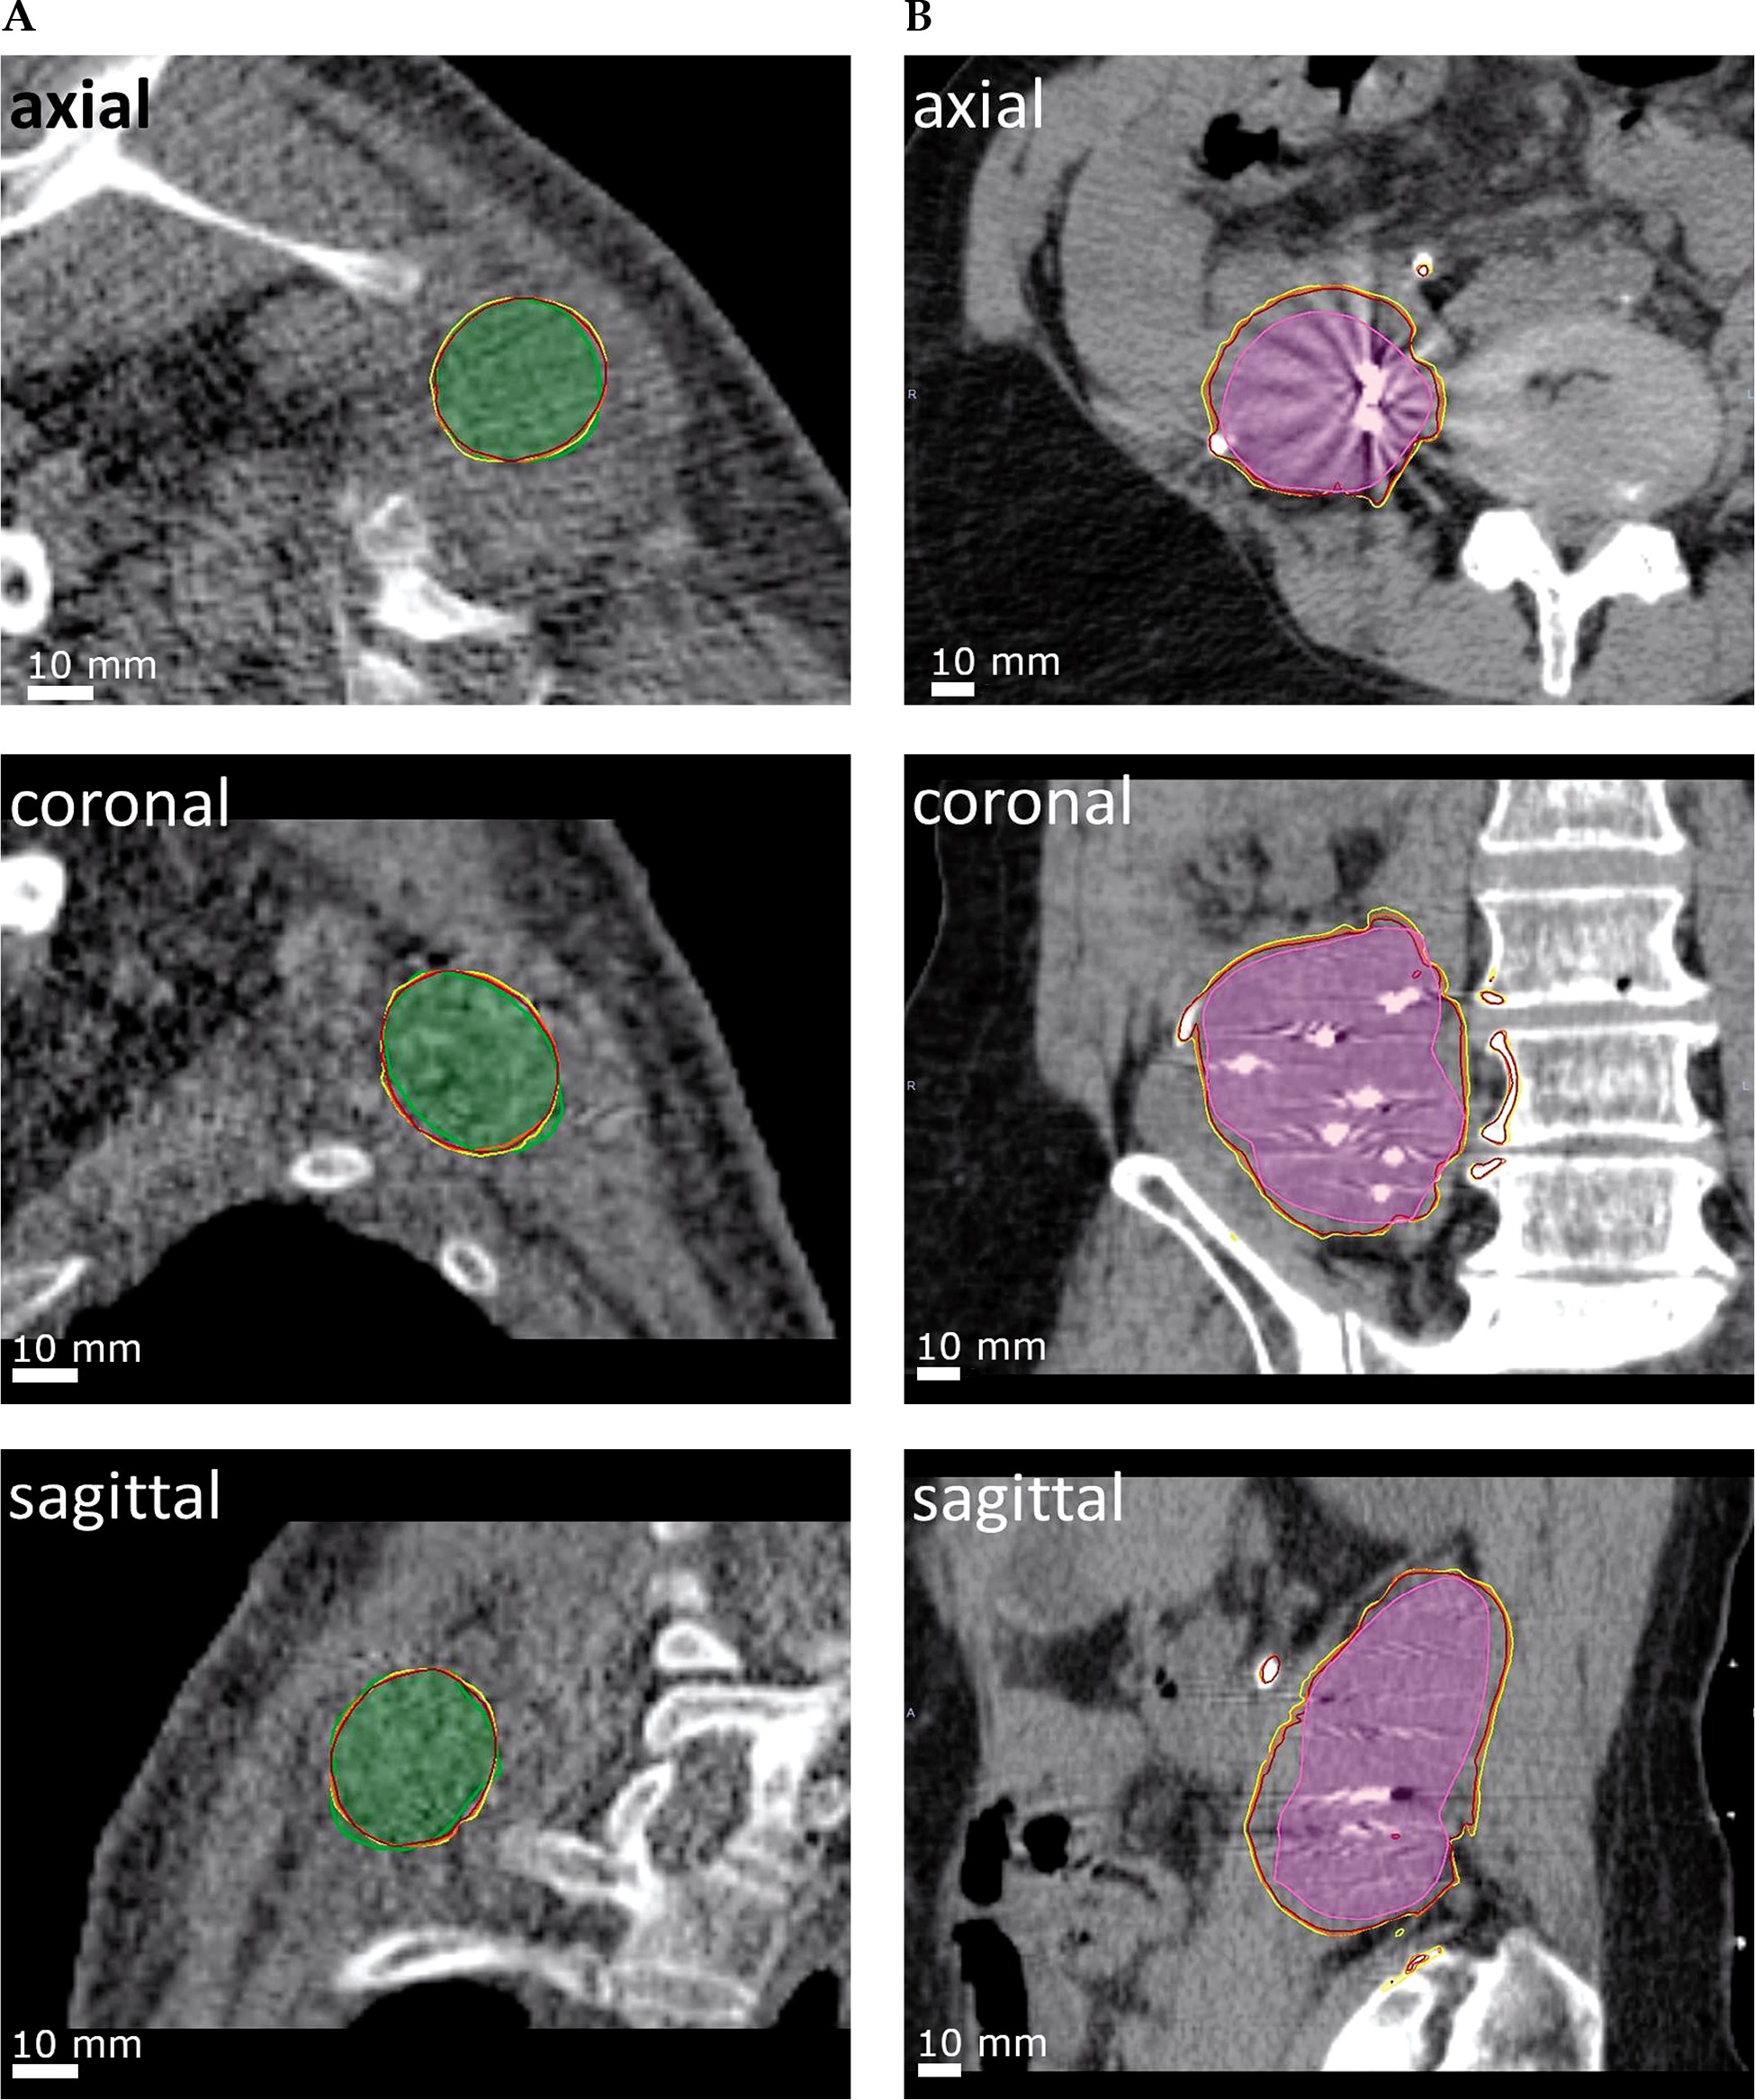

For all cases of simulated EBT, either the prescribed dose or a dose greater than the D90 obtained by PSI was reached. In 8 cases, the D90 acquired with EBT met the prescribed dose, exceeding it by an average of 4.7% (SD = 3.9), with a maximum of 12.6%. The prescribed D90 was not achieved in 2 cases, but still exceeded the D90 obtained with PSI (average, 21.3%, SD = 20.1) relative to the prescribed dose. The CN or COIN, respectively, were greater than 0.6 in all 10 cases, with values between 0.62 and 0.89, and an average of 0.69 (SD = 0.075). Two examples of conformal dose coverage of the PTVEBT by EBT are shown in Figure 3. The mean beam-on treatment time for EBT with the standardized dose of 13 Gy was 27.8 min (SD = 15.6).

Fig. 3

Dose coverage after dwell position summation. Shown are two exemplary cases. A) For the first case (also displayed in Figure 2), a CN of 0.89 was achieved for a PTV in the left shoulder region (green). B) For the second case, a COIN of 0.63 was achieved for a PTV in the retroperitoneal space (pink). Isodose lines of 90%, 95%, and 100% of the prescribed dose displayed in yellow, orange, and red, respectively